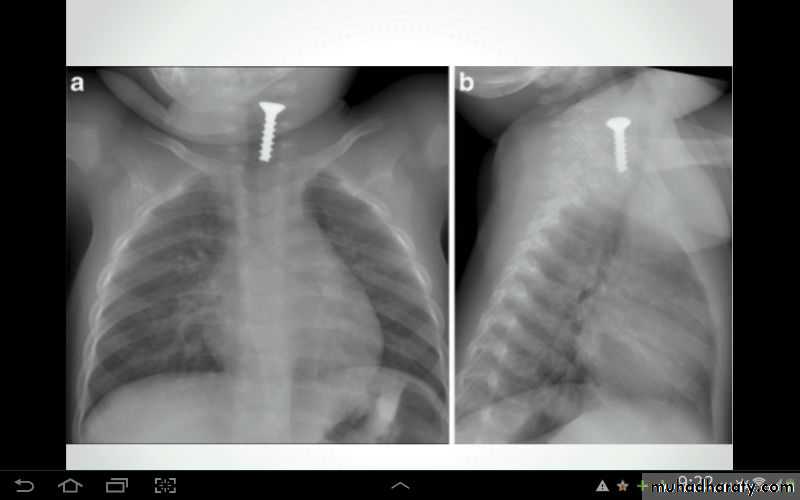

Foreign body in right bronchus

Foreign body in bronchus